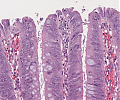

A70 Adenokarzinom des Kolon

Tumordrüsen mit deutlicher Kernpleomorphie

A70 Adenokarzinom des Kolon

Klein- und großdrüsige Tumordifferenzierung an der Invasionsfront